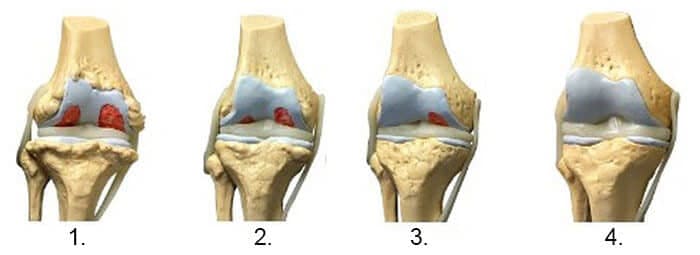

1. Nedostatok výživy kĺbov. Tkanivo chrupavky je zničené.

2. Obnovenie chrupavkového tkaniva kĺbu po 2 týždňoch používania Steplex.

3. Obnovenie chrupavkového tkaniva kĺbu po 3 týždňoch používania Steplex.

4. Zdravý kĺb po ukončení používania Steplexu.